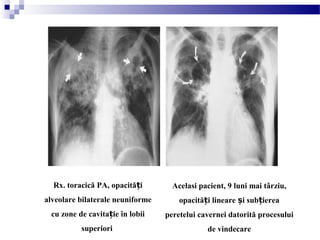

Rx. toracică PA, opacită iț

alveolare bilaterale neuniforme

cu zone de cavita ie în lobiiț

superiori

Acelasi pacient, 9 luni mai târziu,

opacită i lineare i sub iereaț ș ț

peretelui cavernei datorită procesului

de vindecare

(infiltrate i caverne bilaterale ale lobilorș

superiori)